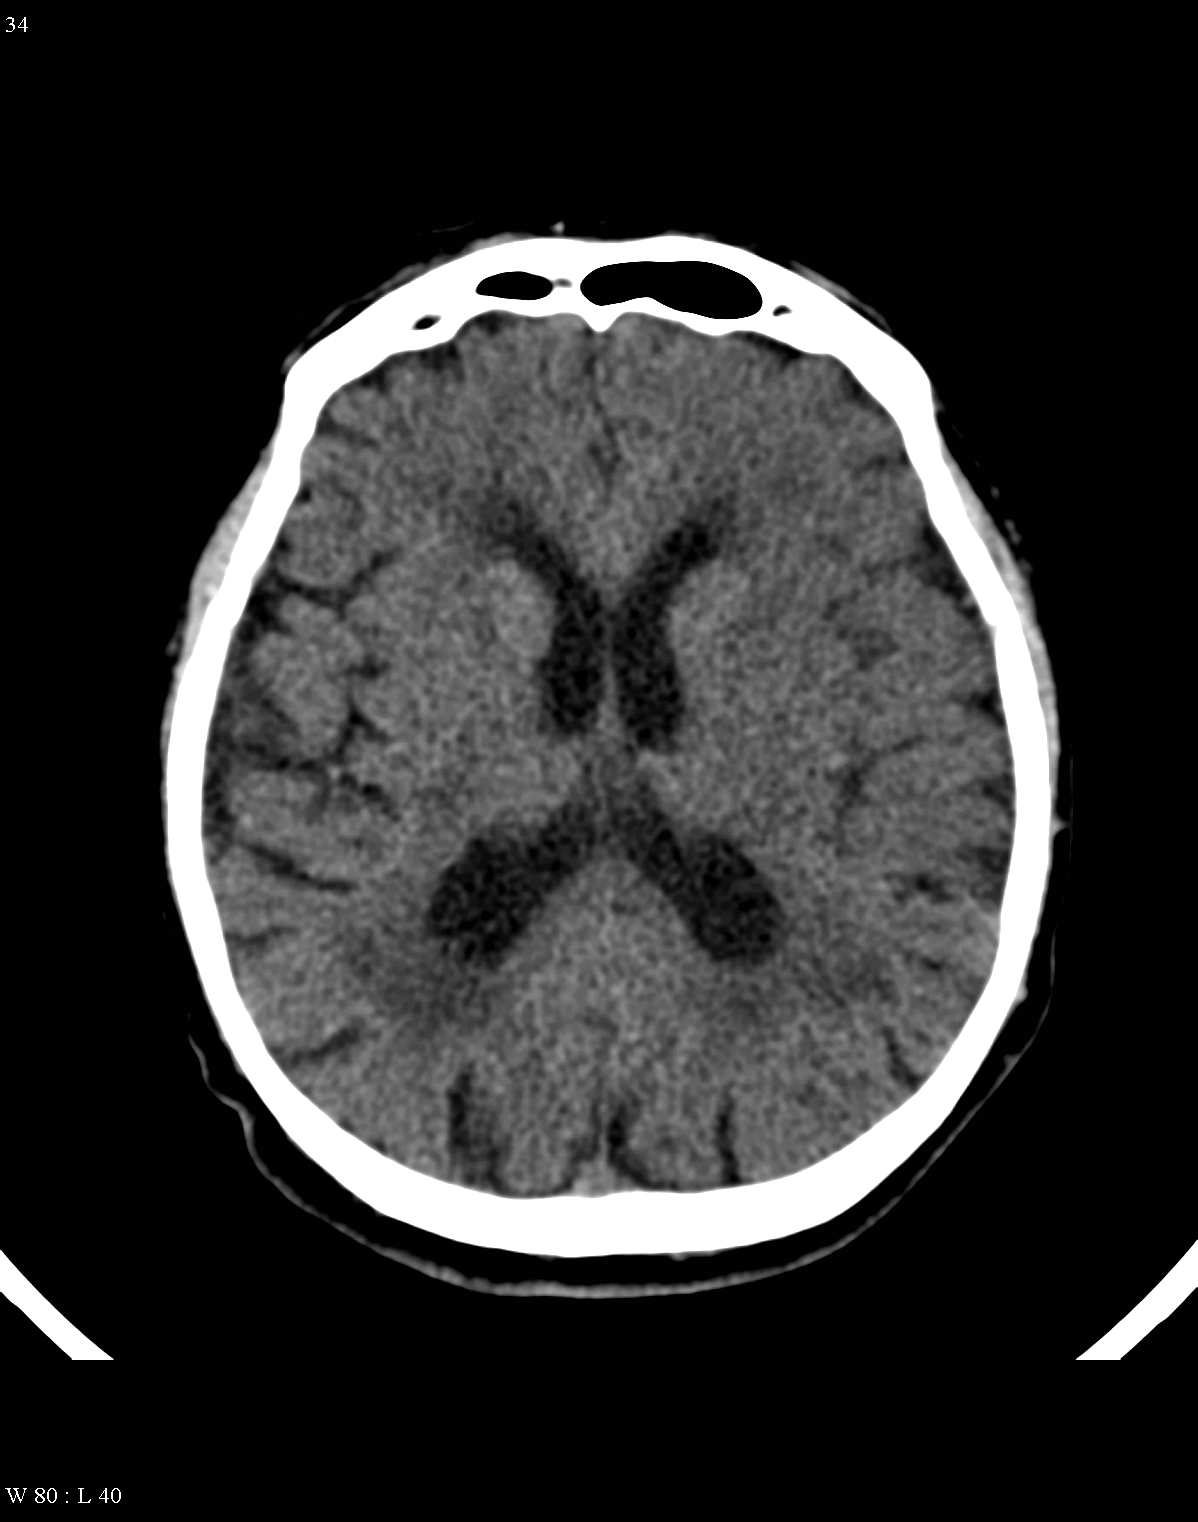

In acute phase (12-24 hours after the occlusion of the middle cerebral artery) on CT hypodense basal ganglia, the loss of cortical white-grey matter differentiation and sulcal effacement are the characteristic imaging findings.

On MRI, diffusion restriction causes hyperintense signal on T2W images. The leptomeningeal border of the infract zone will show contrast enhancement.

After 1-3 days the “mass-effect” of the infarct increases. It is more apparent in case of large territorial infarcts, the sulcal effacement completes, the loss of cortical white matter and grey matter differentiation is more pronounced (especially in the white matter) due to the increased hypodensity. Hemorrhagic transformation in the grey matter (cortex, basal ganglia) can also occur at this stage. It is worth to note, that for hemorrhagic transformation one should not always blame thrombolytic therapy; it rather occurs spontaneously in a great majority of the cases.

After 4-7 days the edema and the “mass-effect” persist, there is a marked hypodensity and even contrast enhanced CT can detect enhancement at the leptomeningeal border of the infarct zone.

Within 1-8 weeks contrast enhancement and mass-effect still persist. Later a slow regression in the mass-effect can be noted. In children (transient) calcification can also occur.

In the chronic phase of the infarct (months to years) the hypodensity of the lesion (CT) reaches the level of the cerebrospinal fluid. There is no more contrast enhancement, the lesion is well differentiated and it degenerates into a cyst secondary to encephalomalacia. The brain parenchyma experiences a volume decrease due to the degeneration (sometimes calcifications can occur at the marginal border of the infarct).